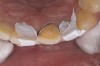

Figure 1 Normal overjet/overbite of anterior teeth

Figure 1

Acid dissolves the palatal enamel of upper anteriors, thus exposing the underlying dentin. This makes teeth appear higher in chroma and leads to hypersensitivity as well as supraeruption of opposing incisors. Clinically, this restricts the space needed to restore lost palatal tooth structure (Figure 1 and Figure 2).